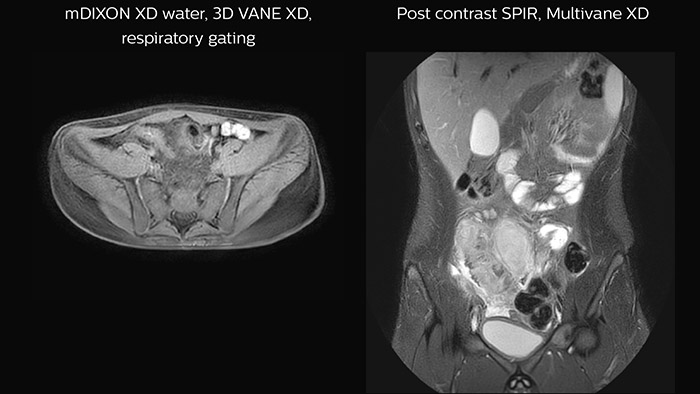

Crohn’s disease in the terminal ileum A large abscess is visible near the terminal ileum, in the middle of the coronal image.

Features that provide remarkable benefits to Dr. Junge include Compressed SENSE, which allows to elevate spatial resolution, signal and scan time. MultiVane XD and 3D VANE XD employ radial k-space sampling and help to mitigate motion artifacts and improve robustness for different contrasts and for all age groups. The mDIXON FFE and mDIXON TSE methods nicely address challenges in fat-free imaging and provide multiple contrast types from one single scan. The achievable large field of view (FOV), high resolution and flexible echo times are certainly a huge benefit in examining children.